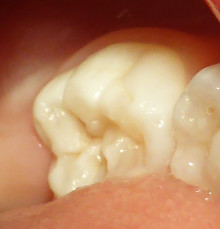

三歳の女の子の奥歯です。

写真のように、でこぼこしています。